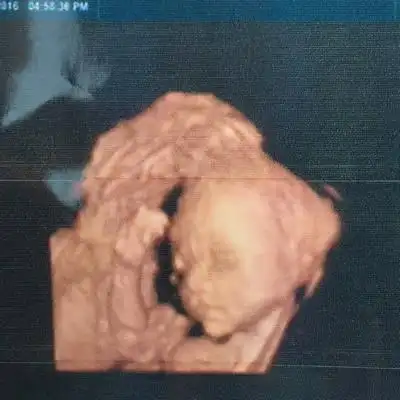

前两天做的四维,四维图上看起来正常,可是放大的照片看起来像兔唇,问

兔唇俗称是唇裂,是一种先天性的疾病,在怀孕的时候就形成的.

胎儿双侧唇裂四维成像图

大家帮忙看一下是兔唇吗?

(e)四维彩超图像显示正中唇裂图6图6四维彩超唇裂四维彩超的优势四维

四维照片宝宝这样算兔唇吗